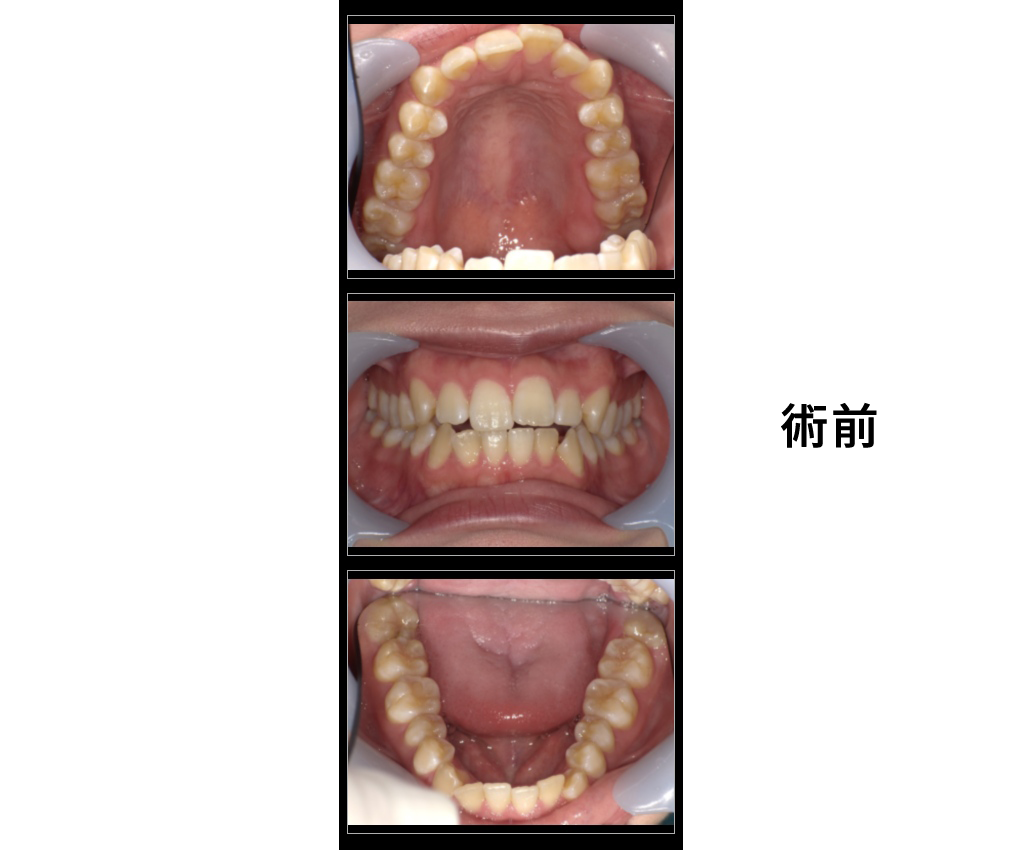

女性50歳

治療内容:定期検診希望だが歯並びが気になる

→歯周治療後にインビザラインGOにて矯正治療

金額:診断22000円、矯正440000円

来院理由:全体的に診てほしい

施術の副作用(リスク):

痛みや違和感を感じることがあります。歯が一時的に動揺することがあります。

咬みにくさをかんじることがあります。